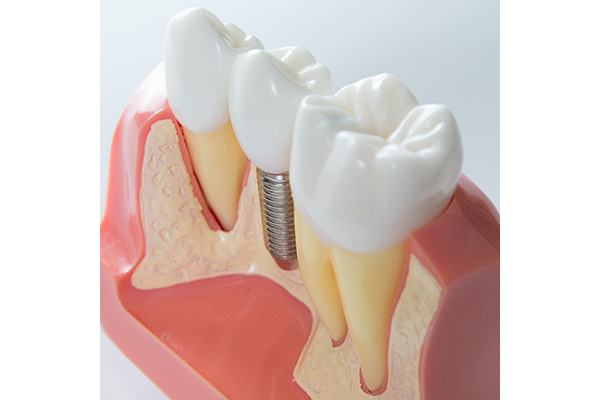

L’implantologia è quel ramo dell’odontoiatria che si occupa di interventi in grado di colmare quelle esigenze estetiche di pazienti che presentano denti mancanti e non vogliono ricorrere a ponti fissi e protesi, generalmente poco pratici. Scopo della chirurgia implantare è ripristinare la masticazione e l’estetica della bocca del paziente mediante il posizionamento di protesi su radici artificiali fissate all’osso della mandibola o della mascella, chiamate impianti dentali.

In poche parole viene inserita una “radice artificiale” nell’osso sottostante la gengiva e sopra di essa viene posizionata una corona in ceramica in totale armonia con la dentatura adiacente.